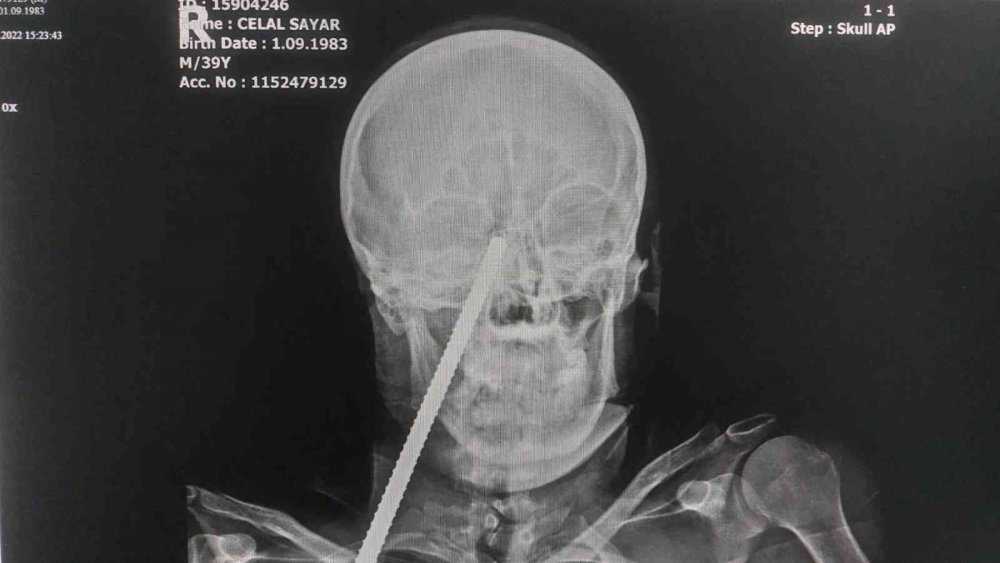

Yüzüne saplanan demirle hastaneye kaldırıldı

Edinilen bilgiye göre, Giresun'da çalıştığı inşaatta demirin üzerine düşen Celal Sayar'ın (39) yüzüne inşaat demiri saplandı. Yüzünde demir saplı halde Giresun'daki hastaneye kaldırılan Sayar, ilk müdahalesinin ardından demirin yüzünden çıkartılması için Samsun'a sevk edildi. Celal Sayar, Samsun Eğitim ve Araştırma Hastanesinde ameliyata alındı. Yüzündeki demir çıkartılan Sayar, daha sonra hastanenin yoğun bakım servisinde tedavi altına alındı.